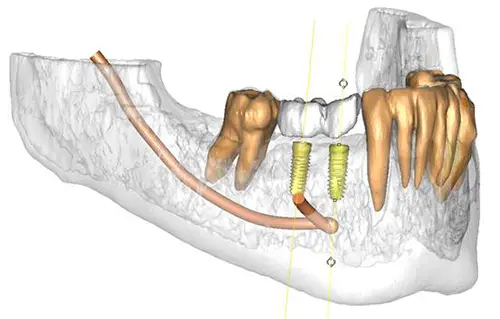

CTデータを用いて、コンピューター上で精密なシミュレーションを行います。

事前のCTシミュレーションをもとに作製したサージカルガイドを使用し、位置・角度・深さを精密にコントロールしながら埋入します。